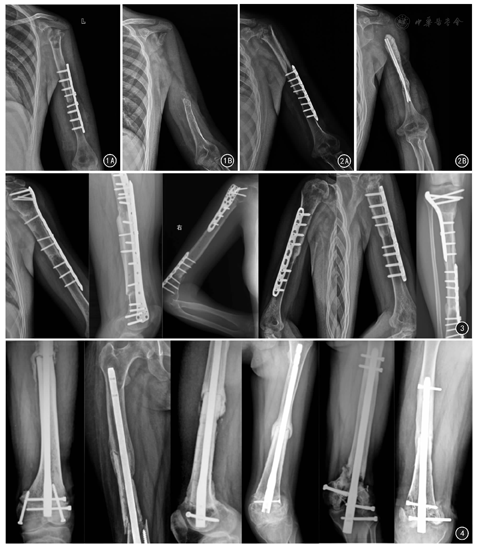

17例患者术后随访2~10(4.8±1.6)年。未愈组10例中,男6例、女4例,年龄12~45岁,异体骨长度8~28 cm;钢板螺钉内固定2例,髓内针内固定8例,均接受化疗。10例中,随访期间发生异体骨骨折4例,其中2例(3、4号)重新植骨内固定术、1例(16号)行人工假体置换术、1例无症状者(10号)未经干预继续随访;异体骨感染2例(14、17号)接受了异体骨取出术(图1、图2);余下4例骨未愈合的患者(1、6、11、13号)未见其他并发症,无不适特殊症状,继续随访。见表1。

愈合组7例患者平均骨愈合时间15~43(27.0±10.5)个月,其中男3例、女4例,年龄14~42岁,异体骨长度9~20 cm;钢板螺钉内固定6例,髓内针内固定1例。均接受化疗。见表1。

未愈组与愈合组各临床特征比较,除内固定方式差异有统计学意义(P=0.015),其他临床特征差异均无统计学意义(P值均>0.05)。见表2,图3,图4。